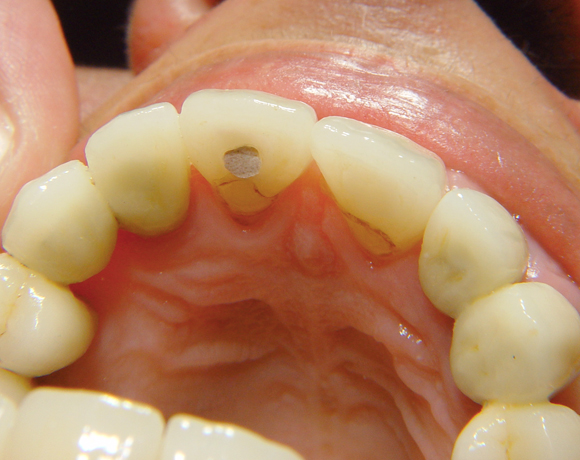

Bei diesem Patientenfall musste nach Neuüberkronung der Frontzähne eine Wurzelbehandlung erfolgen. Um der Gefahr aus dem Weg zu gehen, dass die neue Krone abbricht, da sehr wenig eigene Zahnrestsubstanz nach der endodontischen Behandlung übriggeblieben war, wurde der Zahn nachträglich mit einem Dentinpost versorgt.